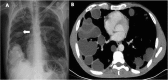

Hydatid disease is a worldwide zoonosis endemic in many countries. Liver echinococcosis accounts for 60-75% of cases and may be responsible for a wide spectrum of complications in about one third of patients. Some of these complications are potentially life-threatening and require prompt diagnosis and urgent intervention. In this article, we present our experience with common and uncommon complications of hepatic hydatid cysts which include rupture, bacterial superinfection, and mass effect-related complications. Specifically, the aim of this review is to provide key imaging features and diagnostic clues to guide the imaging diagnosis using a multimodality imaging approach, including ultrasound (US), computed tomography (CT), magnetic resonance (MR), and endoscopic retrograde cholangiopancreatography (ERCP).